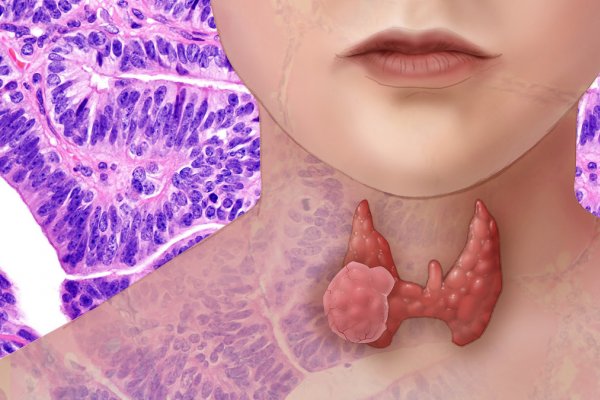

Nema više tableta za probleme sa štitnjačom: OVO JE PRIRODNO RJEŠENJE za taj problem!

Probleme sa štitnom žlijezdom nipošto ne zanemarujte, tako mogu dovesti do štetnih posljedica. Bitno je da na vrijeme primjetite neke simptome i počnete adekvatnu terapiju. Simptomi problema sa funkcijom štitne žlijezde: Nesanica Nagle promjene raspoloženja, […]